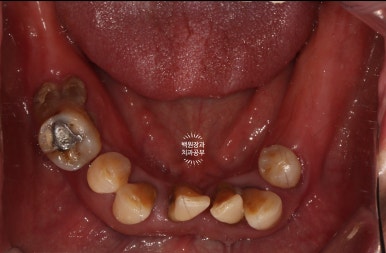

구강내 교합면 사진입니다.

파노라마 엑스레이상에서 많은 치아가 있어보이지만,

실제로 대부분의 치아는 많은 양의 치석이 침착되어 만성치주염의 주소견인 흔들림을 보여주고 있었습니다.